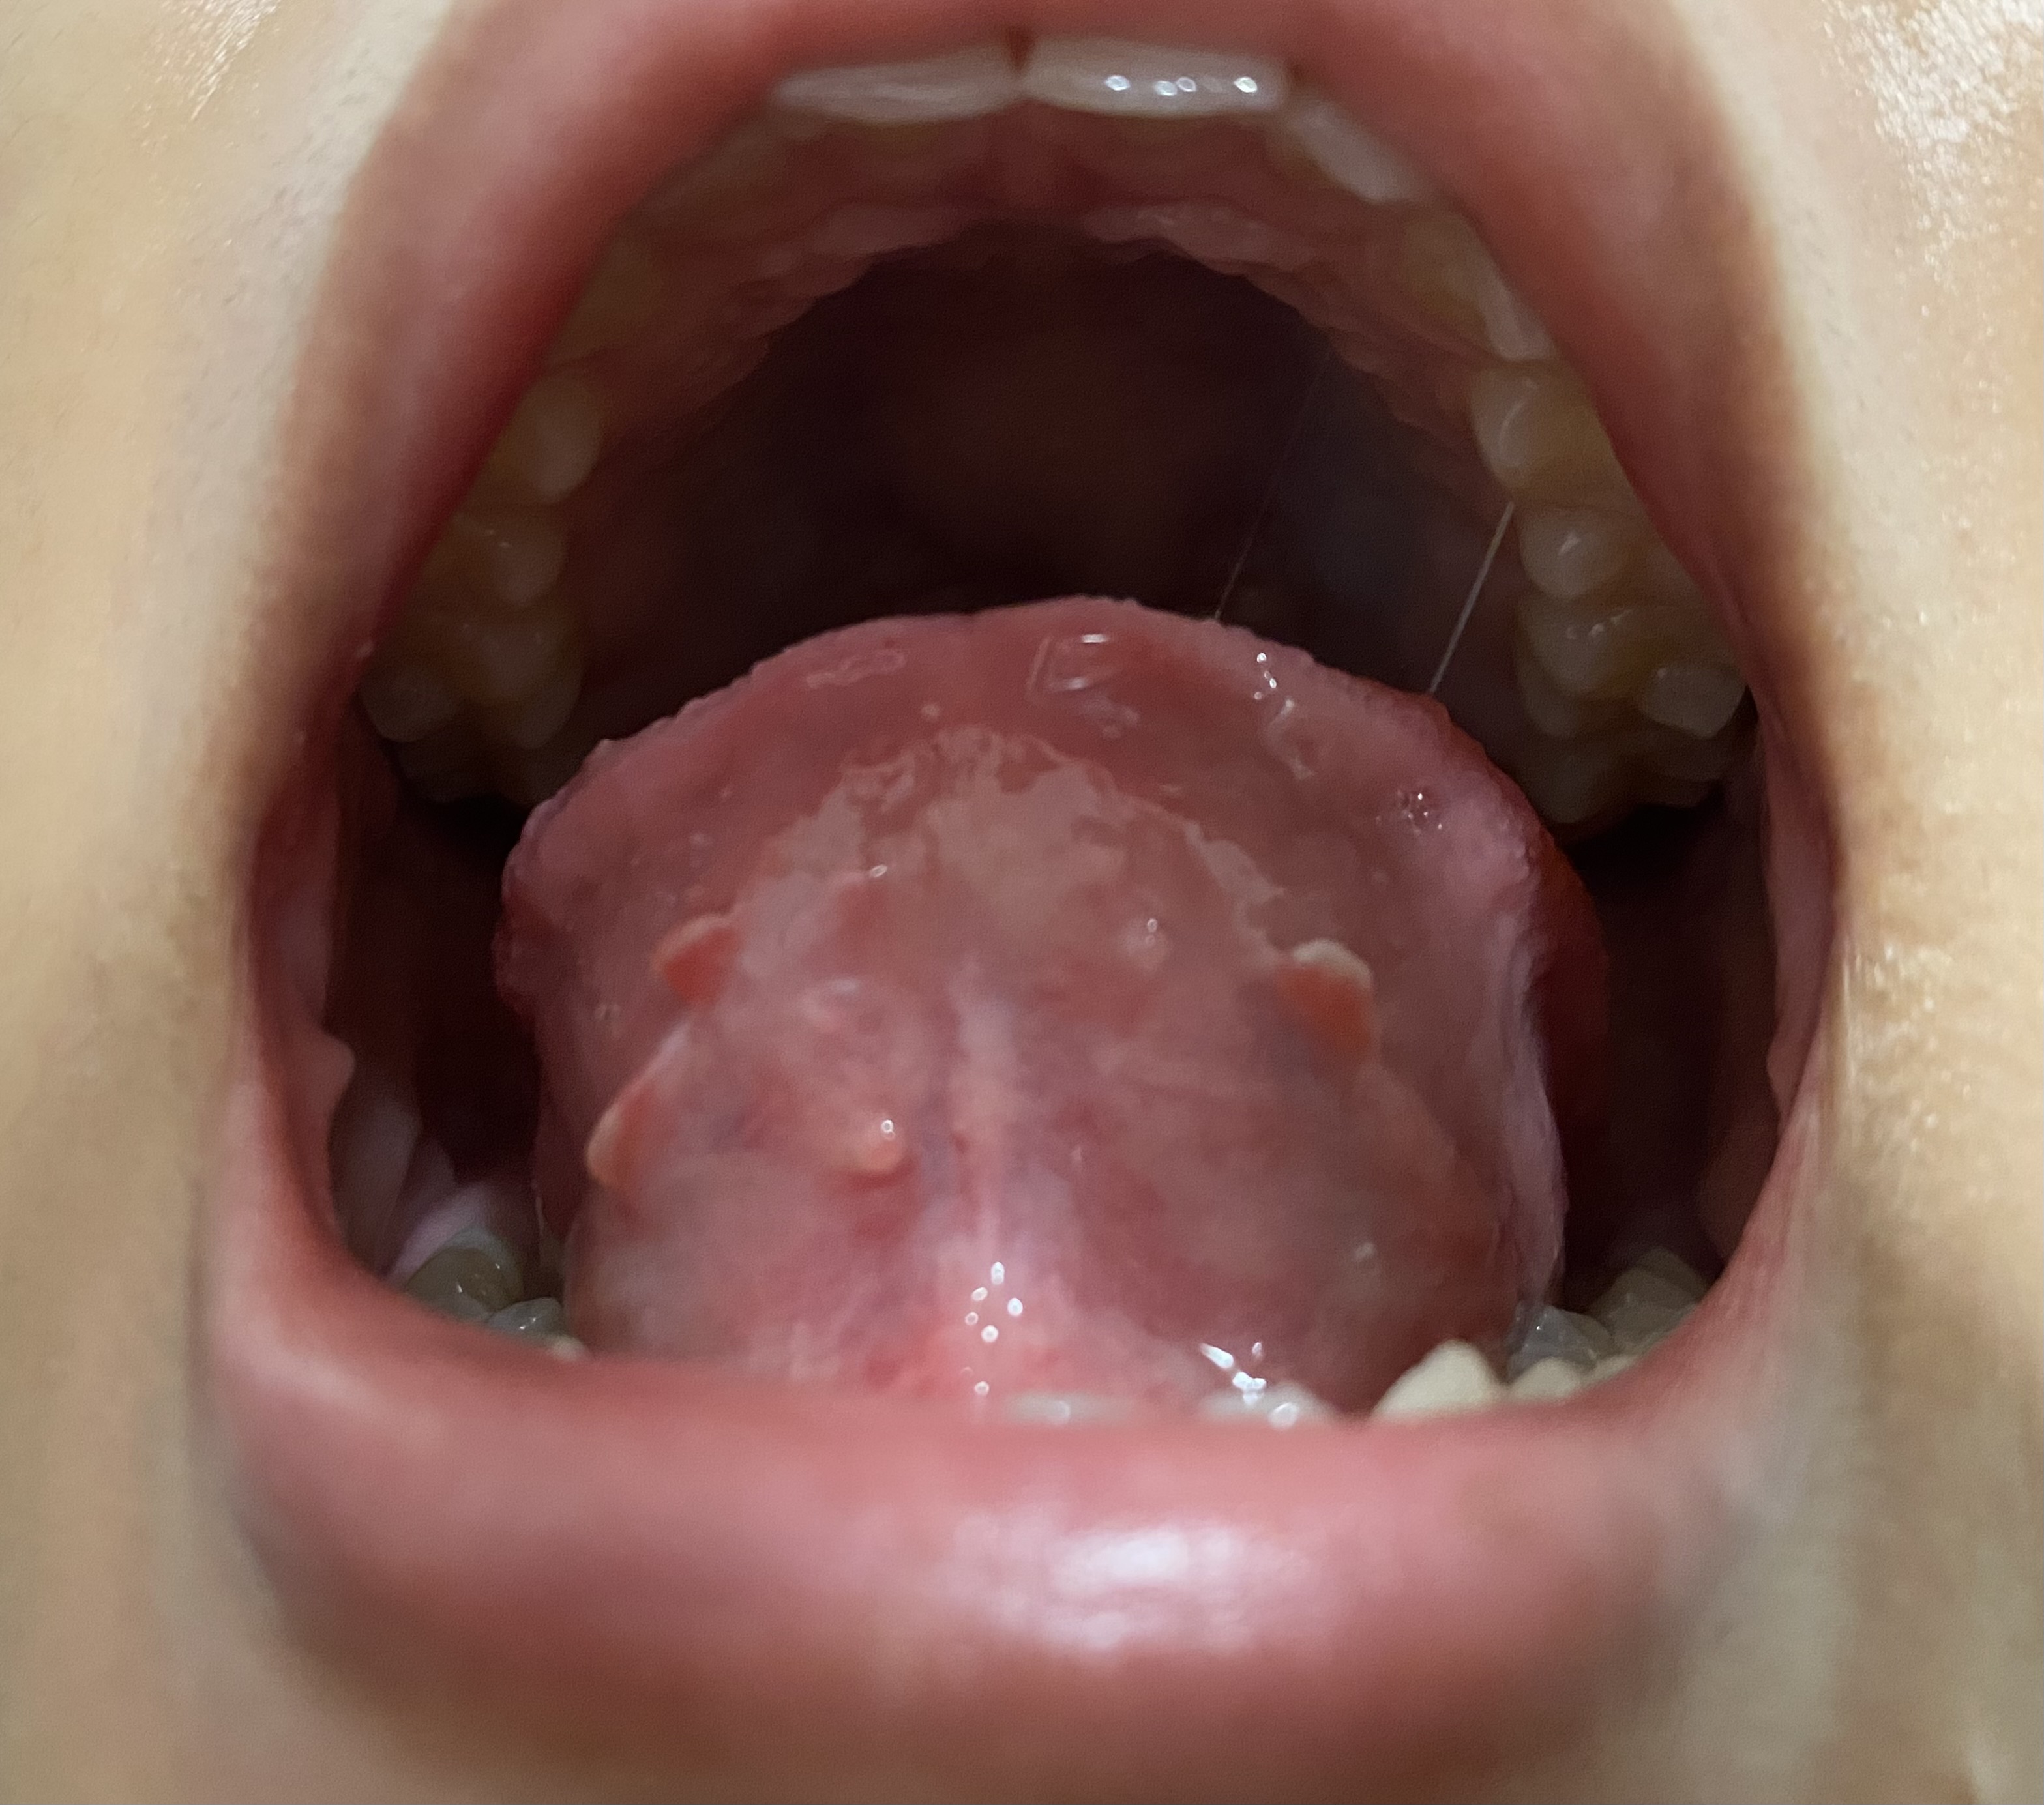

ช่วงนี้รู้สึกแปรงฟันแล้วแสบปากมากๆเลยค่ะ แสบจนน้ำตาไหลเลยก็มี แปรงฟันเลือดออกทุกครั้งเลยด้วยค่ะ กินผลไม้พวกสตอเบอรี่ก็แสบค่ะ ตอนไม่ได้กินอะไรก็รู้สึกเจ็บๆอยู่นิดหน่อยค่ะ พอมาลองส่องดูแล้วเจอเหมือนเนื้อๆงอกออกมาแบบในรูปเลยอะค่ะคุณหมอ อยากทราบว่ามันเกิดจากอะไรได้บ้าง แล้วต้องรักษายังไงได้บ้างคะ

ติ่งงอกที่เห็นเป็นปกติครับ

แต่ใต้ลิ้นมีฝ้าขาวผิวอักเสบ อาจเกิดจากแพ้อาหารหรือขาดวิตามิน เบื้องต้นลองใช้ kamillosan M พ่นวันละสามครั้งครับ ถ้าเจ็ดวันแล้วยังไม่ดีขึ้นให้ไปพบแพทย์หูคอจมูกครับ